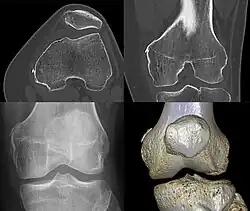

Diagnosis is typically made on radiographs demonstrating the Pellegrini-Stieda syndrome sign accompanied by pain or restriction of range-of-motion of the knee joint.[2] Pellegrini-Stieda syndrome sign is typically described by a longitudinally linear opacity, which is a process that is describes characteristic of calcification in the soft tissue located medial to the medial femoral condyle.[2] This calcification seen on imaging represents the ossification of the medial collateral ligament, which typically does not develop until approximately three weeks after the initial injury.[2]It is important to note to distinguish this radiographic finding from that of a medial femoral condyle avulsion fracture, which is an injury in which a pulling force of a tendon or ligament fractures away a piece of the bone from its attachment site.[2]

The initial injury to the knee, whether resulting from macro- or repetitive microtrauma, leads to the same result: calcific ossification of the soft tissue structures surrounding the medial femoral condyle.[2] This sprain or tear in the medial collateral ligament leads to inflammation of the area. The bodies inflammatory response lead to an immune response to try to repair leading to an abnormal healing process. The abnormalities lead to a disposition of calcium at the tear site of the medial collateral ligament which over time hardens to form a bony mass called heterotrophic ossification. As healing continues, the fibrocartilage or other disorganized tissue becomes calcified, and over weeks to months, it ossifies, forming bone-like material at the MCL attachment site.[5]

The calcification seen on imaging represents the ossification of the medial collateral ligament which typically does not develop until approximately three weeks after the initial injury.[2]